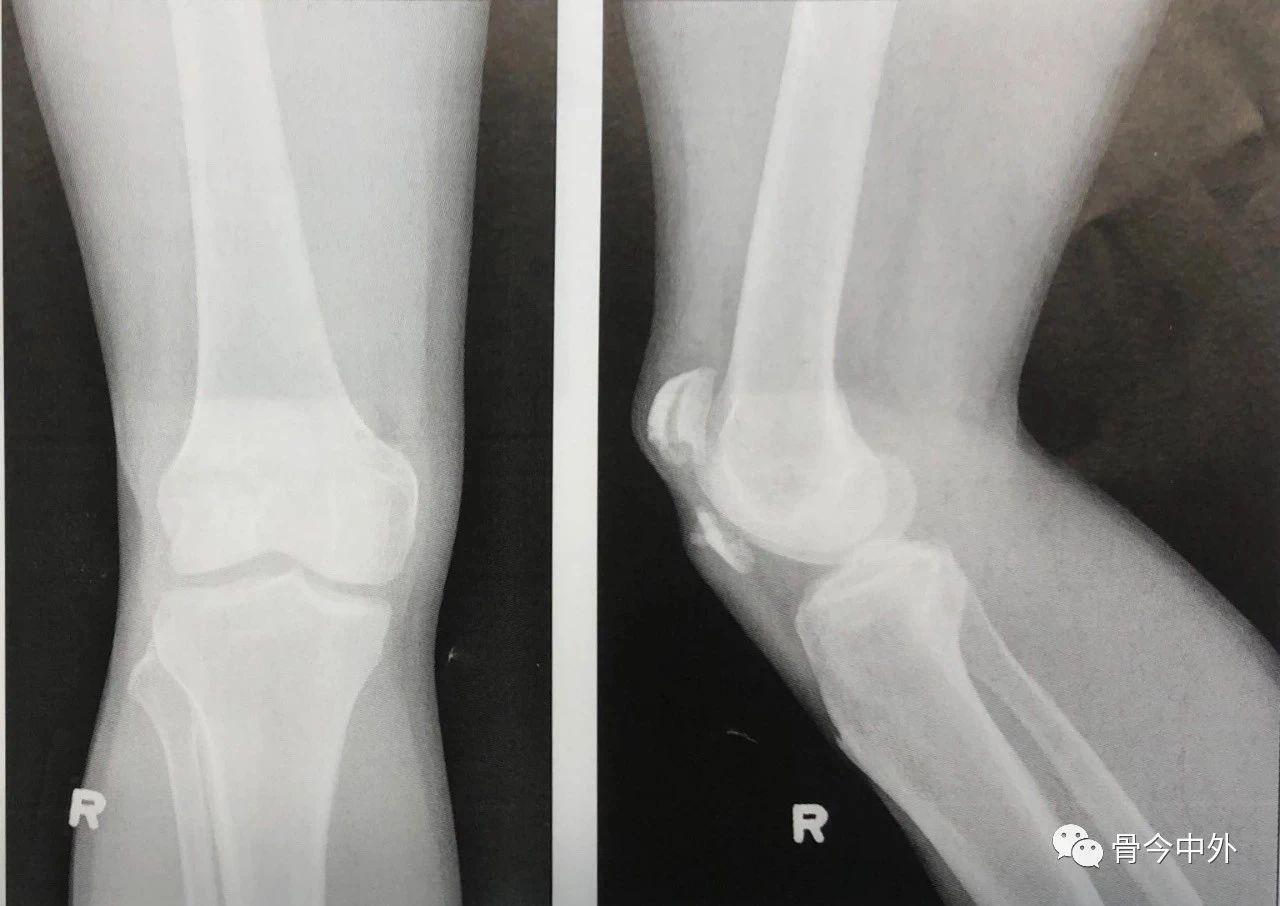

2.钢丝拧得过紧会导致骨折再次移位或者使骨折进一步加重。3.两平行克氏针的末端剪断后在张力环上翻转180”,上下两端埋入骨内以防止其移位(图7)。

图7